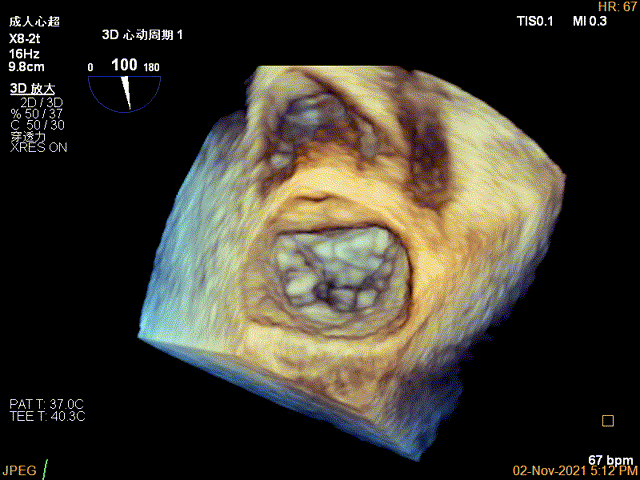

术前超声评估结果

3D-color MV view:大量反流,起源于1区

3D视图菲薄的卵圆窝,穿刺点位近似于3点位